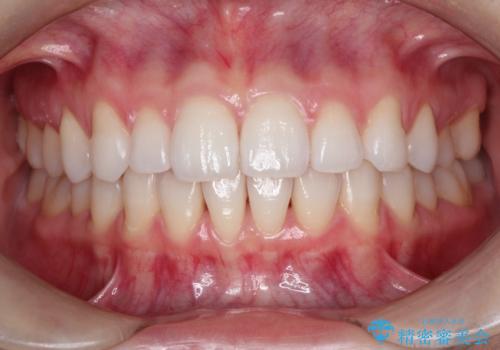

インビザラインで出っ歯を改善する 抜歯をしないinvisalign治療

- 1年5ヶ月

- 非抜歯・遠心移動による前突の改善をマウスピースにて計画した。

非抜歯矯正の場合、大きく前歯を下げることはできませんが、奥歯の遠心移動や歯のサイズダウンにより歯軸を立て、見かけ上の出っ歯感をある程度改善することができます。